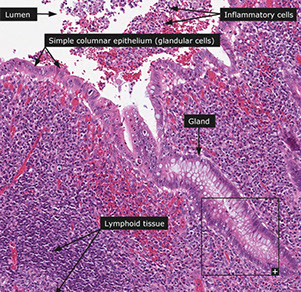

Appendix histology

This wormlike (vermiform), 7-10 cm long structure usually comes about 1-3 cm before ileocecal junction at junction of 3 cecal/ ascending colon teniae.

Histo similar to that of large bowel.

From lumen out: Mucosa, Submucosa, Muscularis externa, Serosa

Mucosa

Surface epithelium

- Columnar cells: eosinophilic cytoplasm and basally located nucleus. Includes absorptive cells and M cells

- Goblet cells: mucin droplet stains with PAS and Alcian blue. Seen more often in the crypts than in suface epithelium.

- M (Membranous) cells: Columnar, brush border, surround lymph aggregates to help bring in antigens. Can usually find lymphos between them.

--Usually fewer crypts between these M cells and lymph aggregates than in other parts of the appendix

-Crypts spread more unevenly than in colon. Work in cell renewal.

-- Endocrine cells: Flasked-  to spindle-shaped. May/not have luminal connection, respectively. (+) chromogranin stain. Found isolated/clustered throughout crypts

-- Paneth cells: abundant eosinophilic supranuclear granules. Found in crypt bases. Function unknown.

- Collagenous subepithelial BM. (+) PAS

-Lamina propria: made of collagen, fibroblasts, VANs, numerous lympho cells. Found in center of mucosa, though can be distorted by lymph aggregates.

-Lymph aggegates: absent at birth, peak in 1st decade then diminish. Similar to Peyer's patches in structure/function. though more cells in appendix have IgG than in colon.

-Mucosal neuroendocrine complex: polygonal cells w/ pale granular cytoplasm beneath crypts. Have neurosecretory cells, neurons, and Schwann cells (thus (+) S-100).

-Muscularis mucosae: continuum from colon, though weaker in appendix, to separate mucosa/submucosa.

Submucosa

Collagenous/ elastic fibers w/ fibroblasts between mucosa and muscularis externa. Also see migratory cells, VANs, Meissner's plexus (ganglion cells, Schwann cells, neurons).

Muscularis externa

Thick double sm. muscle (inner circular, AUERBACH, outer longitudinal) that separates submucosa / serosa. Auerbach's plexus found between 2 sm. musc layers.

Serosa

Nonstratified cuboidal mesothelial cells on top of loose CT of subserosa.

- Attachment of fibrofatty mesoappendix lacks a serosa